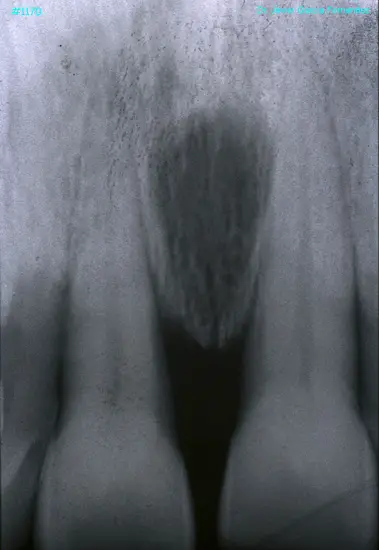

Atlas of Surgical Techniques in Periodontics. Chapter III. Atlas de Técnicas Quirúrgicas en Periodoncia

image588